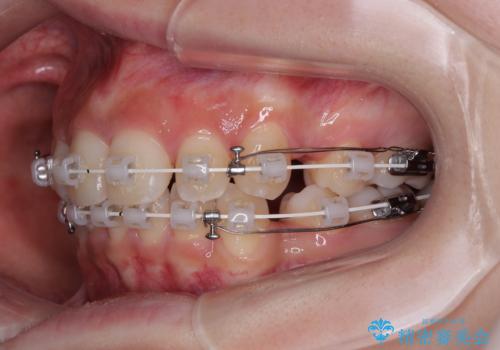

- 矯正装置

- 審美装置

- 治療計画

- 上顎前歯の突出感を気にして来院された患者様です。

上下左右第一小臼歯4本を抜歯して、積極的に口元を引っ込めるよう、ワイヤー装置にて矯正治療を行うこととしました。